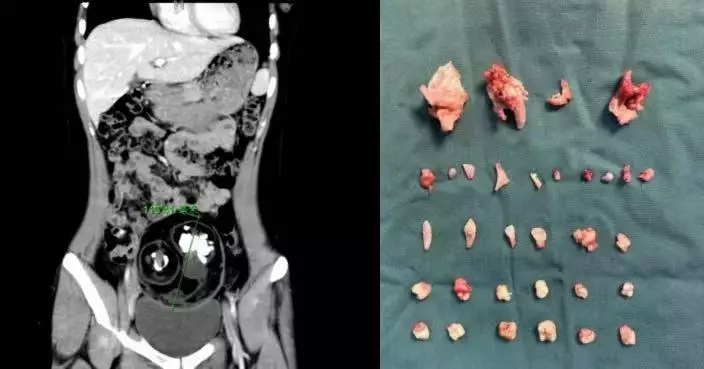

原計劃開刀切除腹部10公斤腫瘤 美婦術前檢查揭懷有身孕奇蹟迎健康男嬰